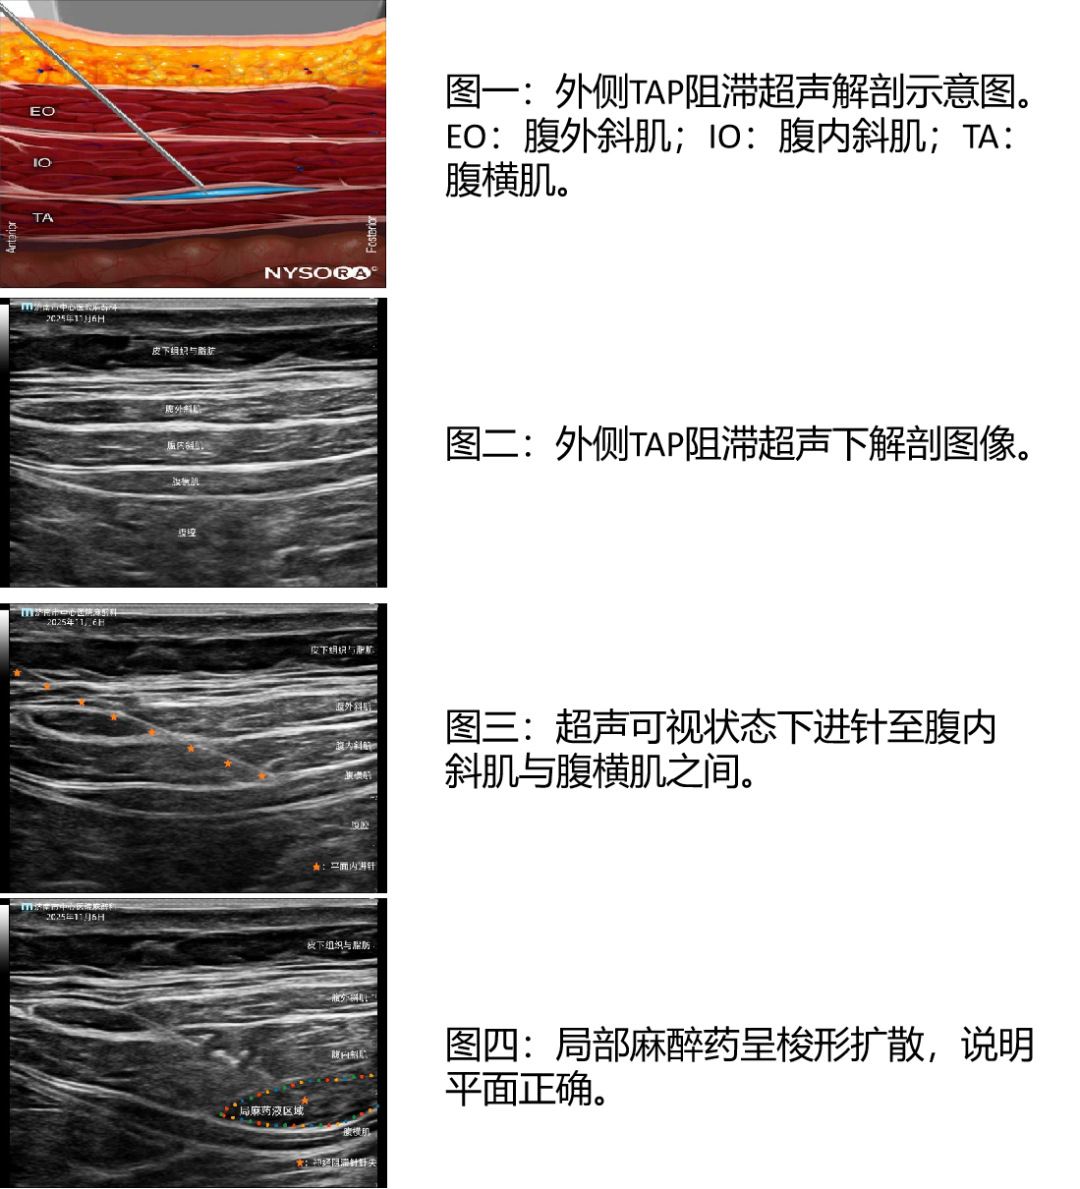

看得见,才安全:在超声屏幕上,我们可以清晰地看到您腹部一层一层的结构——皮肤、脂肪、肌肉、以及那个关键的“药物公寓”(腹横肌平面)。同时,我们能实时看到重要的内脏器官和血管,确保针尖完美避开它们。

看得见,才精准:我们能实时看着针尖到达目标“夹层”,然后精准地注入药物,并看到药物在正确的平面内扩散开来,形成完美的“镇痛雨伞”。